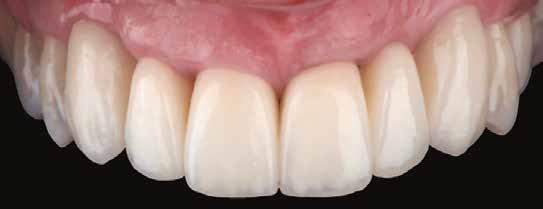

10. a ábra: Végleges lítium-diszilikát koronák. – 10. b ábra: Végleges monolitikus cirkónium-dioxid korona. – 11. a–b ábrák: Klinikai megjelenés tizenkét hónap elteltével. 12. a–b ábrák: Tizenkét hónapos kontrollröntgen-felvételek.